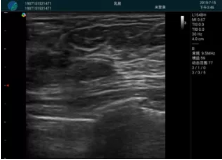

可視化甲狀腺穿刺引導

頸動脈血流充盈飽滿,無外溢

肝內(nèi)血管顯示清晰,血流敏感無外溢